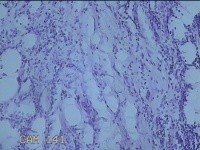

右侧会阴部结节

性别

女

年龄

31岁

临床诊断

皮脂腺囊肿

一般病史

发现右侧会阴部结节2个月。

标本名称

大体所见

灰白暗红色结节1.7x1.3x0.3cm一个,表面糜烂,切开结节呈实性,切面灰白暗红色,质软。

图2

炎症性病变。